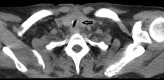

BACKGROUND The role of tracheostomy during the coronavirus disease 2019 (COVID-19) pandemic is still to be determined, and the complication rate of the tracheostomy in COVID-19 patients is still unknown. Postintubation tracheal stenosis is a well-known risk of prolonged endotracheal intubation, but it is too early to define the existence of any difference among the COVID-19 cohort of patients and non-COVID-19 patients. This report is of 2 cases of COVID-19 pneumonia that required tracheostomy and prolonged endotracheal intubation, which were followed by delayed tracheal stenosis. CASE REPORT Case 1. A 54-year-old male was admitted to our hospital (Biella, Italy) for severe acute respiratory syndrome coronavirus-2 (SARS-CoV-2) infection. The patient underwent orotracheal intubation, progressively improving his breathing function, and was discharged after 20 days. Ten days later, the patient presented with severe respiratory distress. Computed tomography (CT) scan and bronchoscopy showed signs of tracheal stenosis. We administered intravenous steroids for 10 days. The patient showed increasing improvement in his breathing function and was discharged with no other signs of respiratory distress. Case 2. A 43-year-old male was admitted to our hospital for SARS-CoV-2 infection. The patient underwent orotracheal intubation, progressively improving his breathing function, and was discharged after 25 days. Eighteen days later, the patient came to our emergency room with severe respiratory distress. CT scan and bronchoscopy showed signs of tracheal stenosis. The patient had to undergo tracheal resection. CONCLUSIONS The 2 cases presented in this report have shown that even when patients recover from severe COVID-19 pneumonia requiring tracheostomy and mechanical ventilation, tracheal stenosis should be recognized as a potential complication and careful follow-up is required.